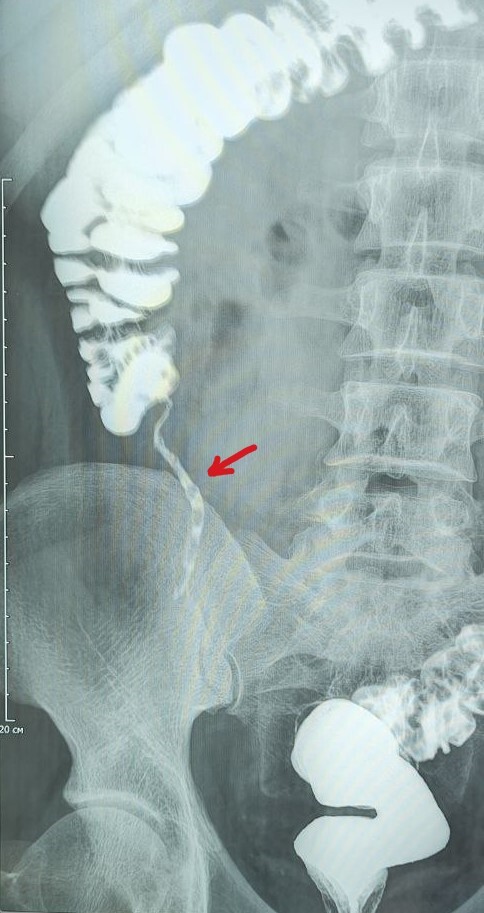

В анамнезе у призывника частые госпитализации( раз в  1-3мес) с такими диагнозами как: кишечная колика, обострение хронического панкреатита, холецистита, лечение с временным положительным эффектом. В дальнейшем призывника попадает на ирригоскопию.

Описание: Аппендикс контрастирован неравномерно, с участками чередования контраста и газа, в проекции шейки стенотическое сужение. Заключение: Признаки хронического аппендицита.

Призывнику присвоена категория годности по статье  61Г(временные функциональные расстройства органов пищеварения после острого заболевания, обострения хронического заболевания или хирургического лечения), отсрочка дана для оперативного лечения-аппендэктомии.